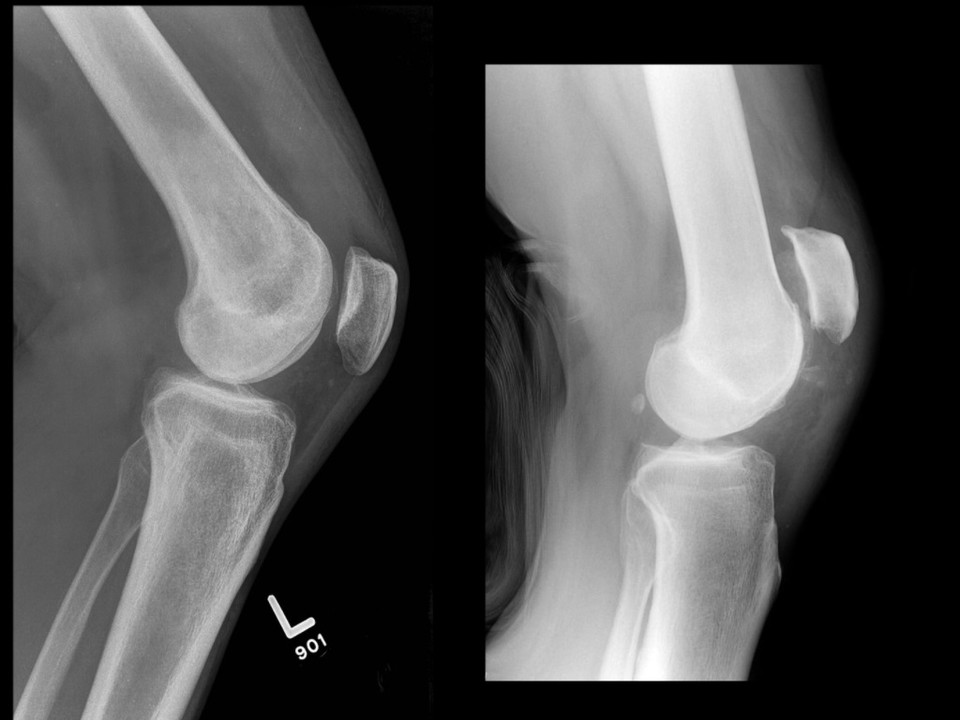

A patellar tendon rupture occurs when the tendon connecting the patella to the tibia is torn. This can be a partial tear, where some tendon fibres remain intact, or a complete rupture, where the tendon is entirely severed. A complete rupture typically requires surgical intervention to reattach the tendon and restore full knee function.

• Difficulty or inability to straighten the leg.

• A visible gap or indentation below the kneecap.

Surgery is often required for complete ruptures to reattach the tendon to the kneecap and restore function:

• Tendon Repair Surgery: Suturing the torn tendon to the kneecap using anchors or stitches.